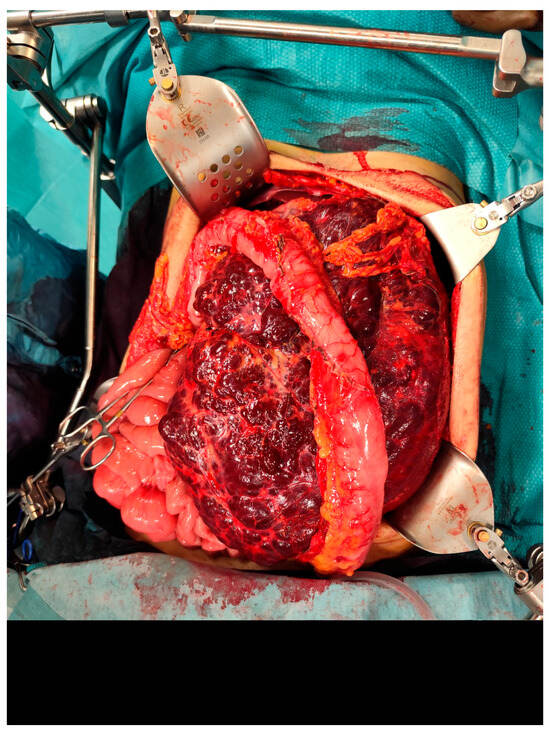

Postoperative pathological examination revealed a brownish, multiloculated cystic lesion measuring 18 × 17 × 30 cm, with areas of hemorrhage and multiple whitish calcified components. Subsequent analysis identified these calcifications as phleboliths, formed secondary to intralesional thrombotic events.

Figure 5. The resected specimen.